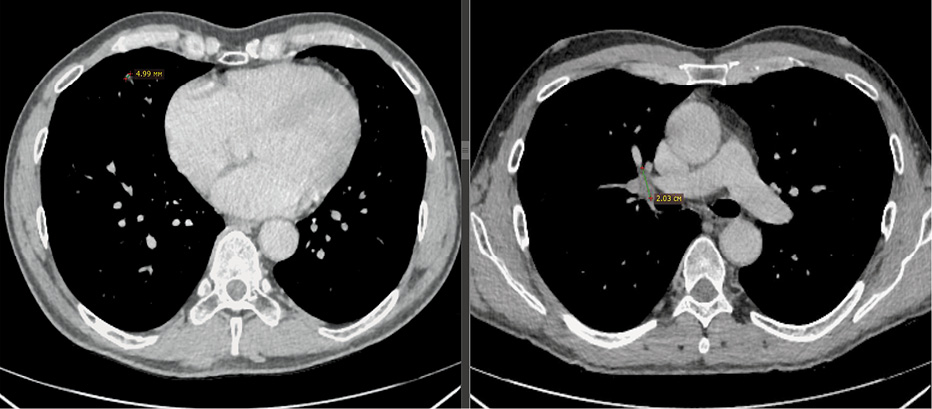

Рис. 1. Пациент 2. Компьютерная томография органов грудной клетки от 06.02.2020 г. (до начала лечения).

Fig. 1. Patient 2. Chest computed tomography,06.02.2020 (before the beginning of the treatment).

Рис. 2. Пациент 2. Компьютерная томография органов грудной клетки от 07.04.2021 г. (через 1 год после начала терапии осимертинибом). Полный ответ.

Fig. 2. Patient 2. Chest computed tomography,07.04.2021 (one year after the beginning of therapy with osimertinib). Complete response.